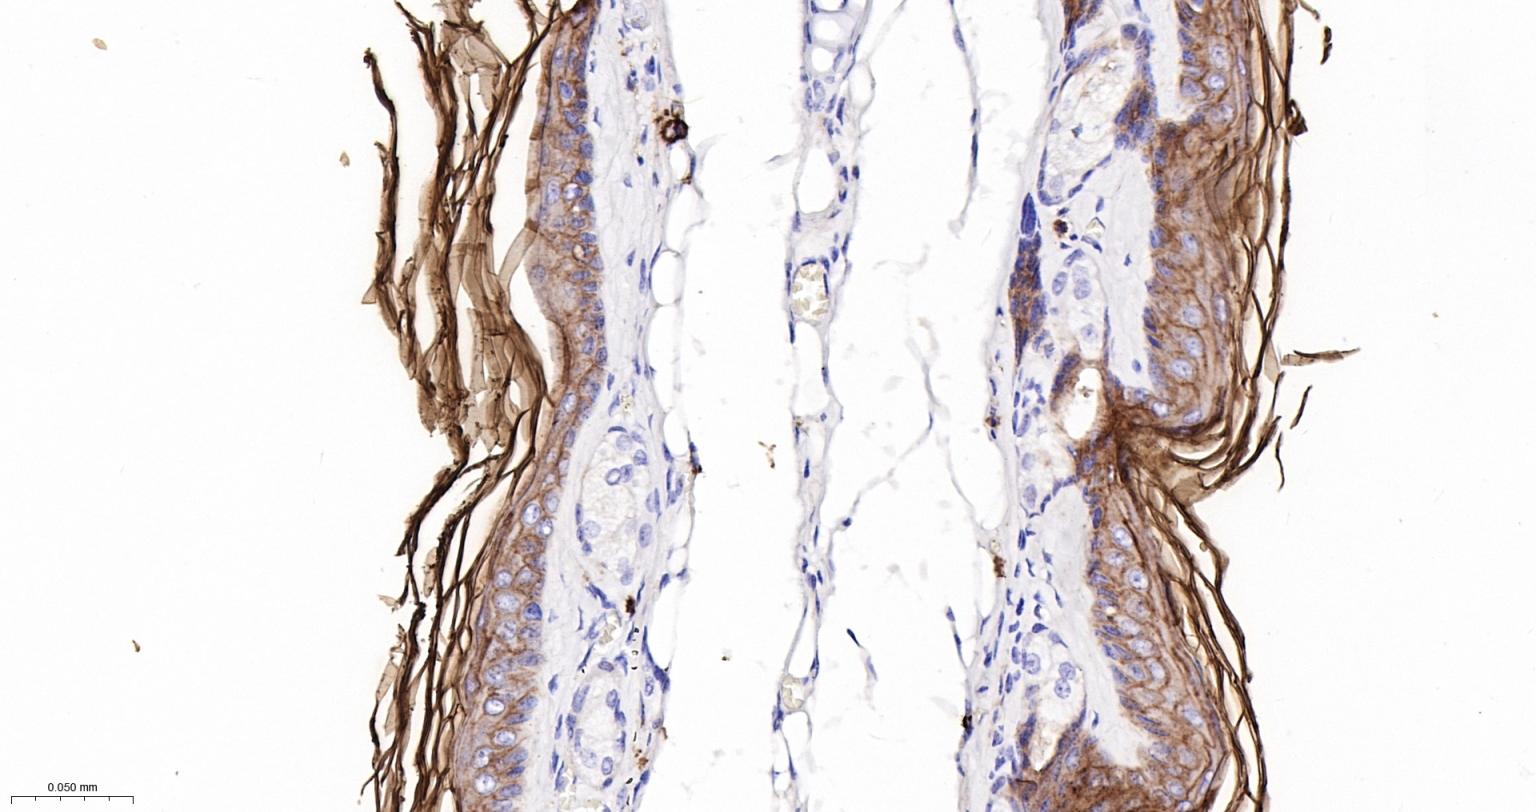

Paraformaldehyde-fixed, paraffin embedded Human Skin; Antigen retrieval by boiling in sodium citrate buffer (pH6.0) for 15 min; The section was incubated with PERP Monoclonal Antibody, Unconjugated (bsm-61725R) at 1:200 overnight at 4°C, followed by conjugation to the bs-0295G-HRP and DAB (C-0010) staining.